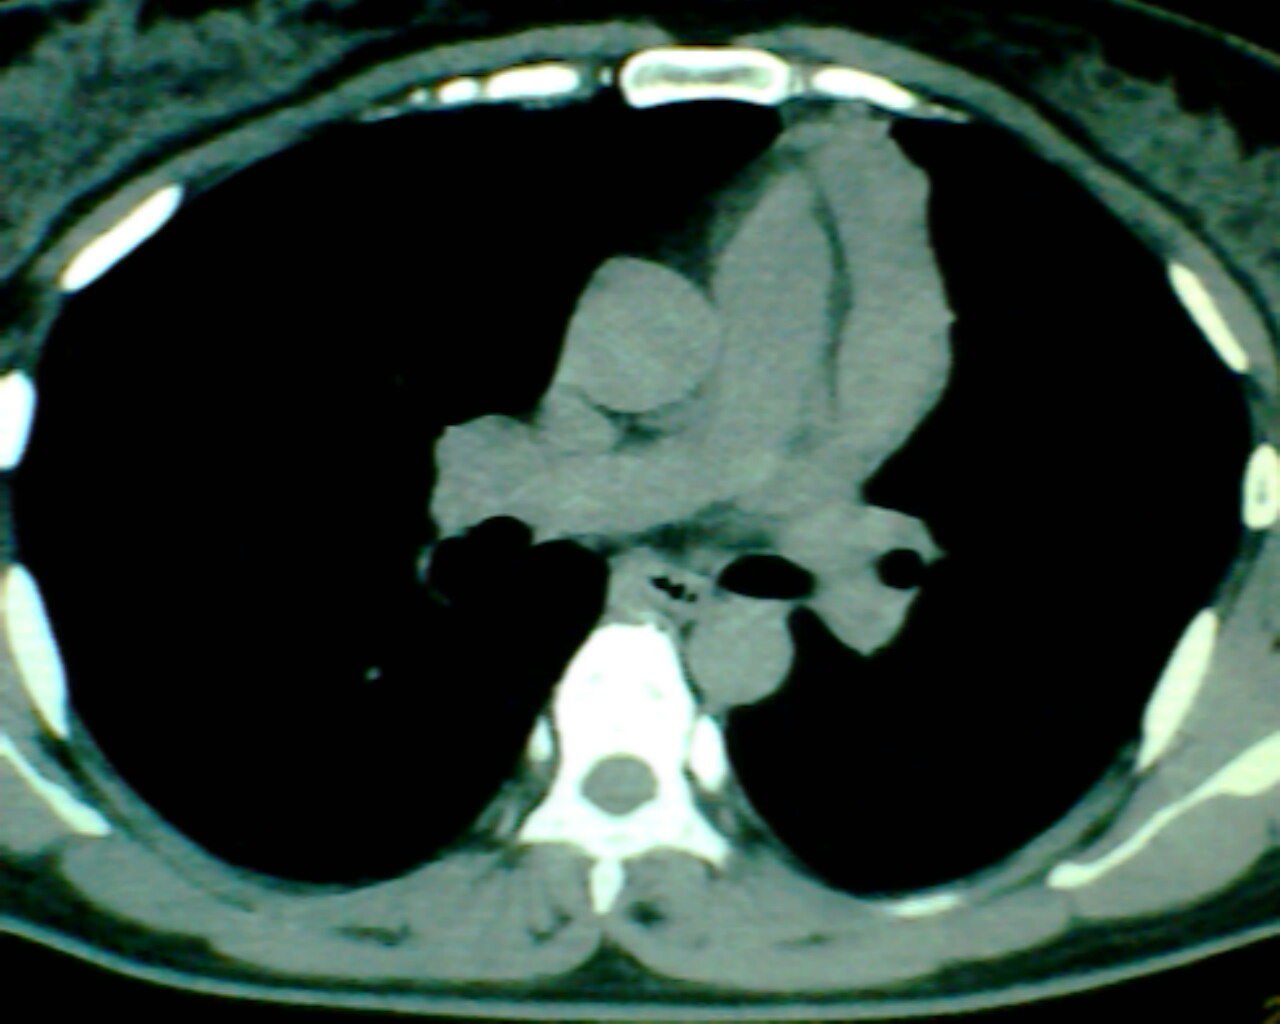

以下是引用狙击手在2007-4-10 22:46:00的发言:[br]考虑:左上纵膈旁型肺癌。理由:1,肿块与纵隔间有分隔;2,肿块呈分叶状;3,肿块突出面圆心在肺内;4,纵隔左移;5,纵隔内器官未见受压征象。